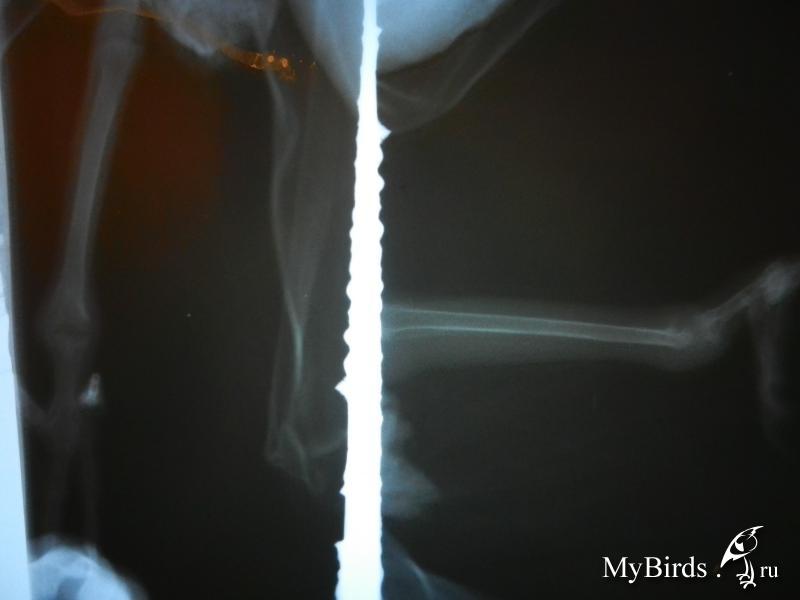

Pussycat Опубликовано 26 февраля, 2013 Автор #26 Опубликовано 26 февраля, 2013 снимки рентгена прилагаю, может по ним что скажут специалисты, а то наши врачи ни черта не понимают. Сам он с удовольствием кушает сегодня даже с рук поел, по нему видно что лапка стала еще больше болеть теперь он совсем на неё ни как не наступает, и предполагаю что он не спит из за неё, т.к. не может сидеть на палочках, даже пить даем сами.

Cheshirski Опубликовано 27 февраля, 2013 #33 Опубликовано 27 февраля, 2013 снимки рентгена прилагаю, может по ним что скажут специалисты, а то наши врачи ни черта не понимают. Сустав сильно воспален.Переломов нет, но от этого не легче.Что с анализами?Птичка уже совсем не может сидеть на жердочку, носом клюет и все, Жако "ест ногами". Возможно, поэтому и исхудал. Кормите насильно - как угодно, со шприца, с руки, с тарелочки - да хоть с бубном вокруг пляшите, если поможет. Пока тощий - лечение впрок не пойдет. В аптеке - инъекционную глюкозу и физраствор, проще в бутылках. Шприцы 10-мл и шприцы инсулиновые со съемной иглой. Маааленькая поправка - не физраствор, а раствор Рингера. И гюкозу 5% только. А так - согласен с MarinaS.если специалист скажет то будем уже уколы делать, Я говорю -НАДО!Все наши ветеринары говорят что нужно зафиксировать сустав чтоб он не шевелился вообще, Это нереально.На сустав попробуйте делать компресс: Все мешать в резиновых перчатках и в них же делать процедуры, т.к. у нас кожа более чувствительна к Димексиду, чем у птиц.Хранить смесь темной закрытой стеклянной посуде или в темноте.Наносить на марлю и прикладывать к суставам на 30 мин. через день. Не наносить на поврежденную кожу. Состав:Димексид - 10мл.Лидокаин 10%- 2мл.(амп.)Дексаметазон - 1мл.(амп.)Линкомицин 30% - 6мл.(амп.)Все средства - из человеческой аптеки.

Pussycat Опубликовано 28 февраля, 2013 Автор #34 Опубликовано 28 февраля, 2013 Позвонил травматолог по нашему ренгену, сказал что у него рахрушен весь сустав, обычному животному сделали бы операцию а с птицей все печальнее на много,я не хочу ему верить